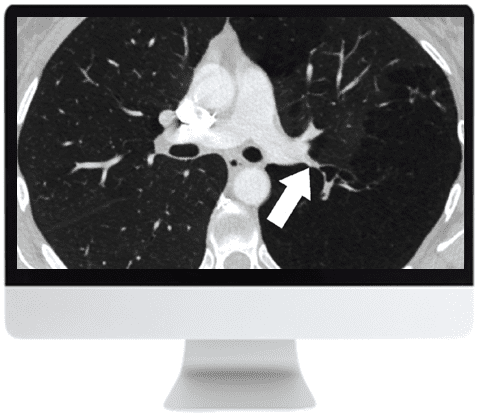

The ARRS Basic Chest Imaging 2019 course provides a thorough introduction to fundamental concepts and updates in chest imaging. Designed for medical professionals, it covers the critical spectrum of thoracic diseases and the technological advances shaping diagnostic approaches. The course emphasizes a practical, case-based framework to improve clinical confidence in interpreting chest radiographs and CT scans.

Through expertly delivered video content, participants will explore topics such as airway assessment, atelectasis identification, infection imaging in immunocompromised patients, pulmonary nodule management, and pulmonary embolism evaluation. This offering reflects world-class medical learning — accessible anytime, anywhere — enabling flexible and focused skill development in thoracic diagnostics.

• Assess pulmonary nodules systematically; apply current guideline-based strategies for characterization and management of both solid and subsolid nodules.

• Evaluate nodular patterns on chest CT with attention to common and rare causes, using an anatomical and pattern-based approach.